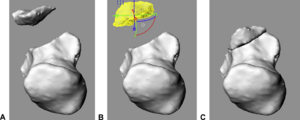

Performance of Single And Multi-Atlas Based Automated Landmarking Methods Compared to Expert Annotations in Volumetric Microct Datasets of Mouse Mandibles

|

Publication: Front Zool. 2015 Dec 1;12:33. PMID: 26628903 | PDF Authors: Young R, Maga AM. Institution: Center for Developmental Biology and Regenerative Medicine, Seattle Children's Research Institute, Seattle, WA, USA. Background/Purpose: Here we present an application of advanced registration and atlas building framework DRAMMS to the automated annotation of mouse mandibles through a series of tests using single and multi-atlas segmentation paradigms and compare the outcomes to the current gold standard, manual annotation. Results: Our results showed multi-atlas annotation procedure yields landmark precisions within the human observer error range. The mean shape estimates from gold standard and multi-atlas annotation procedure were statistically indistinguishable for both Euclidean Distance Matrix Analysis (mean form matrix) and Generalized Procrustes Analysis (Goodall F-test). Further research needs to be done to validate the consistency of variance-covariance matrix estimates from both methods with larger sample sizes. Conclusion: Multi-atlas annotation procedure shows promise as a framework to facilitate truly high-throughput phenomic analyses by channeling investigators efforts to annotate only a small portion of their datasets. Funding:

|

Visualization of the distances between the atlas surface that was landmarked (p90) and four other surfaces constructed. a 50 % Probability surface (p50); b 70 % Probability surface (p70); c Surface thresholded at grayscale value of 35. d Surface thresholded at grayscale value of 55. RMS: Root mean square error. Segmented left hemi-mandibles were imported into 3D Slicer and visualized using a fixed rendering and threshold setting. |